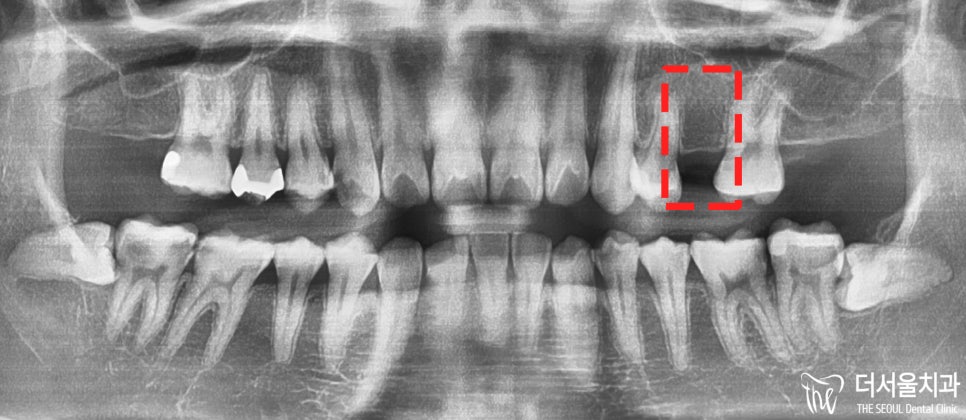

진료 전, 촬영했던 파노라마 엑스레이를 보면

공간 협소 외에는 별다른 문제는 없었습니다.

물론 24, 26번을 지대치로 이용하여

브릿지를 연결하여 기능을 회복할 수 있습니다.

그러나, 20대에 해당하는 젊은 분이었기에

아직 브릿지를 하기에는 너무 젋었죠.

그래서 성남 치아교정을 진행하기로 합니다.